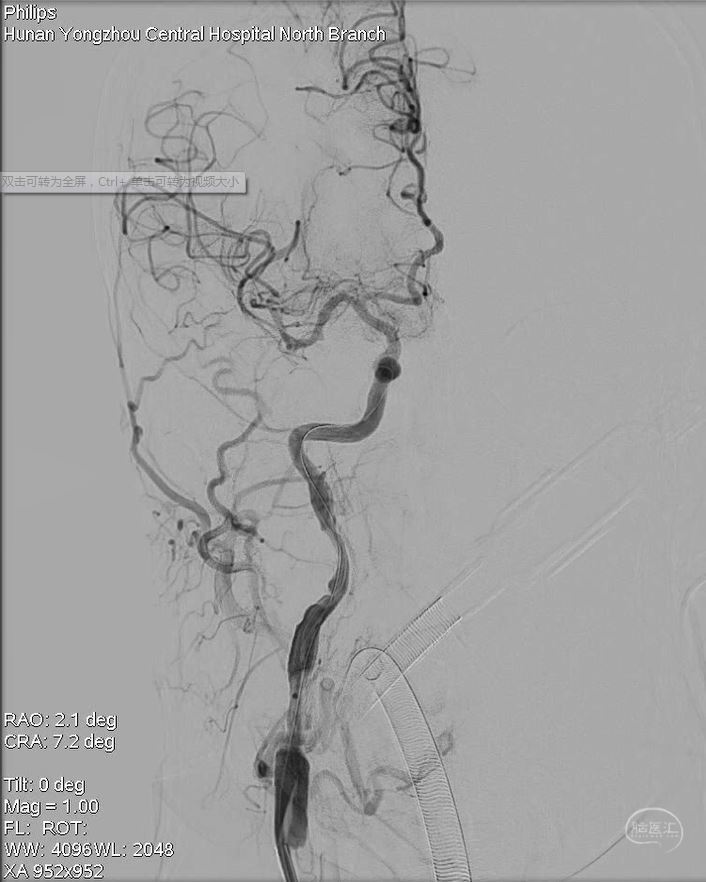

此时颅内血管开通,大脑前血流也满意。C1段管壁不光滑,血流无法维持,拟支架置入。

3.在观察过程中,右侧颈内动脉C1段斑块回缩,血流不能维持,只能再次球囊扩张后置入颈动脉支架。

观察过程中右侧C1再次闭塞,血流不能维持。

只能再次球扩后置入支架。

最后正侧位造影、通路造影、Dyna-CT。手术完成。

正位造影